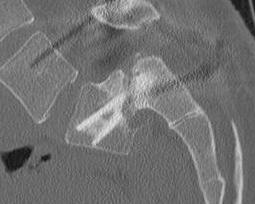

CT scan

Technique

- reverse gantry

Indication

- perform instead of obliques

- oblique x-rays have high radiation dose with little extra information compared with CT

Spondylolysis

Definition

- radiolucent defect of pars

Types

- acute - narrow gap & irregular edges

- pars elongated & thinned

- chronic - wide gap with smooth sclerotic edges